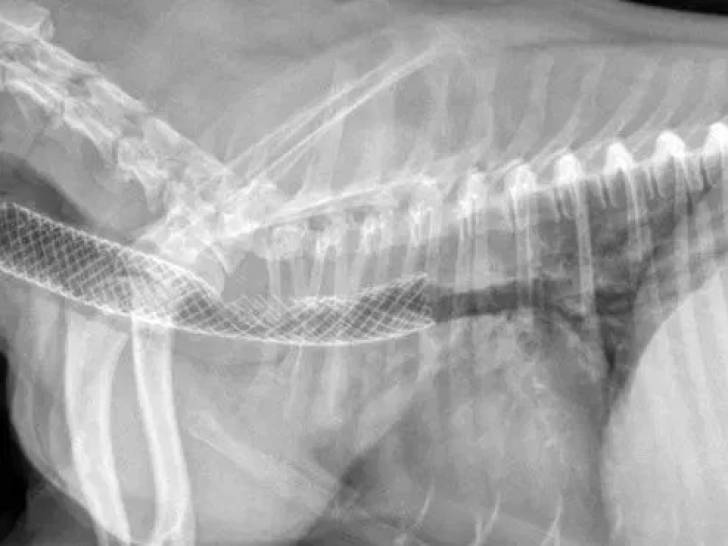

Si l'examen clinique semble indiquer un collapsus trachéal, le vétérinaire réalise alors généralement des radiographies au niveau du cou et/ou du thorax sous différents angles (tant à l'inspiration qu'à l'expiration, normalement) afin de visualiser l'apparence de la trachée. Un scanner et/ou une échographie peuvent également être utiles si les radiographies ne sont pas concluantes. En dernier recours, si un doute persiste, une endoscopie sous anesthésie générale permet de confirmer définitivement le diagnostic.

Si la médication ne suffit pas ou si la trachée est déjà trop affaissée, une opération est la seule solution possible pour qu'il puisse retrouver une respiration à peu près normale. Elle consiste en la pose d'un stent trachéal : il s'agit d'une prothèse tubulaire qui permet de maintenir la trachée ouverte. L'opération se pratique sous anesthésie générale et dure habituellement moins de 15 minutes.

Par la suite, des soins post-opératoires sont requis pendant quelques jours à quelques semaines, notamment pour soulager les douleurs et réduire le risque d'infection. Enfin, un suivi régulier permet de s'assurer que la prothèse est bien tolérée.

En général, le prix d'une opération pour poser un stent trachéal chez un chien est de l'ordre de 1000 à 1500 euros. C'est coûteux, mais cela permet à l'animal de retrouver une capacité respiratoire normale ou quasi normale.